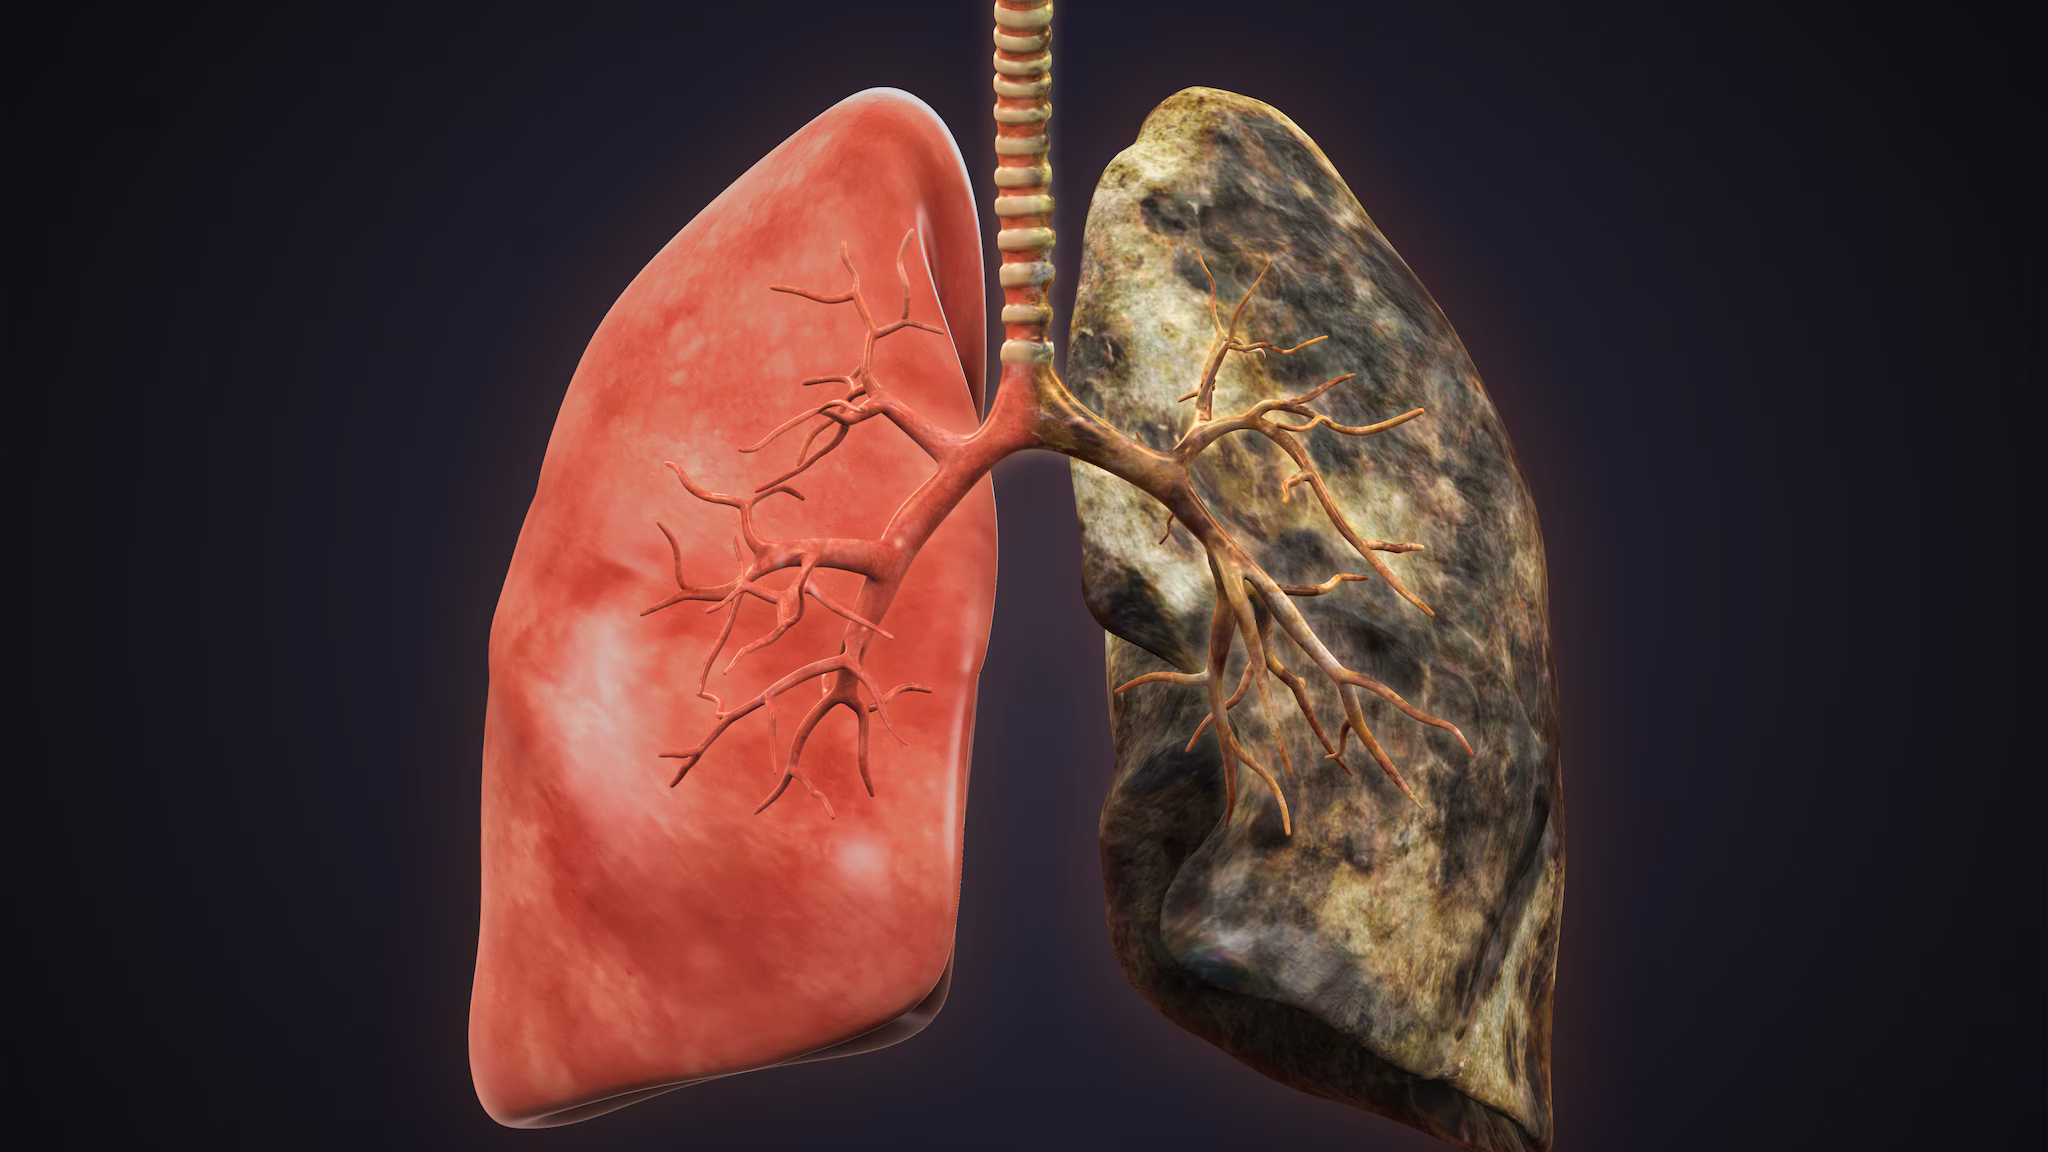

- The pneumoconioses are a group of lung diseases caused by the lung’s reaction when breathing in certain dusts.

- Coal workers' pneumoconiosis (commonly referred to as CWP or black lung) caused by inhaling coal mine dust

Pneumoconiosis typically takes years to develop. However, rapidly progressive forms of silicosis can occur after short periods of intense exposure. When severe, the diseases often lead to lung impairment, disability, and premature death. Pneumoconioses can be avoided through appropriate dust control.